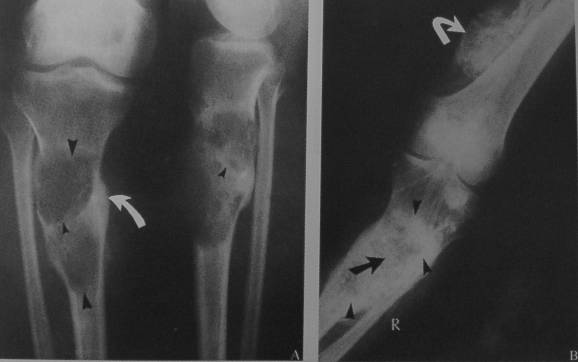

男 26岁

右小腿肿物数年,近期疼痛加重。

胫骨下端骨髓腔内局限性骨密度减低改变,边界模糊,骨皮质未见明显中断,结合病人多年的病史,考虑软组织良性肿瘤压迫吸收临近骨组织。建议mr或ct检查。

1、病史资料:男,26岁.右小腿肿物数年,近期疼痛加重。平片软组织未见明显肿物。

胫骨下段密度减低,呈丝瓜瓤样改变,髓腔稍扩大,皮质略变薄,骨膨胀不明显,无骨变形,考虑骨纤可能

鉴别:内生软骨瘤,钙化不明显,不太支持

病变边缘清晰,似有硬化环。邻近骨皮质连续,未见中断。周围未见软组织肿块。考虑为良性病变。纤维性骨皮质缺损或非骨化性纤维瘤。

x线平片:圆形或卵圆形软组织肿块影,基底部与病骨相连。

肿瘤内可见斑点状或细小结节状钙化。

骨质破坏大多表现为溶骨性地图状或虫噬性破坏,并常伴有层状骨膜反应。